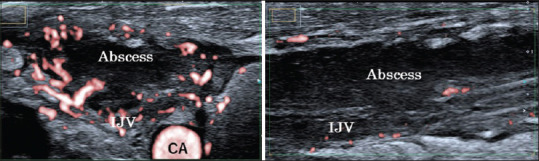

We present a 19-year-old woman, a case of Lemierre syndrome, who presented with fever, sore throat, and left shoulder pain. Imaging revealed a thrombus in the right internal jugular vein, multiple nodular shadows below both pleura with some cavitations, right lung necrotizing pneumonia, pyothorax, abscess in the infraspinatus muscle, and multiloculated fluid collections in the left hip joint. After inserting a chest tube and administering urokinase for the pyothorax, a bronchopleural fistula was suspected. The fistula was identified based on clinical symptoms and computed tomography scan findings. If a bronchopleural fistula is present, thoracic lavage should not be performed as it may cause complications such as contralateral pneumonia due to reflux.

我们为您介绍一名 19 岁女性莱米埃尔综合征患者,她因发热、咽喉痛和左肩疼痛而就诊。影像学检查显示右颈内静脉有血栓,双侧胸膜下方有多个结节状阴影,并伴有一些空洞,右肺坏死性肺炎,脓胸,冈下肌脓肿,左髋关节有多发性积液。在插入胸管并使用尿激酶治疗脓胸后,怀疑出现了支气管胸膜瘘。瘘管是根据临床症状和计算机断层扫描结果确定的。如果存在支气管胸膜瘘,则不应进行胸腔灌洗,因为这可能会导致并发症,如因反流而引起的对侧肺炎。